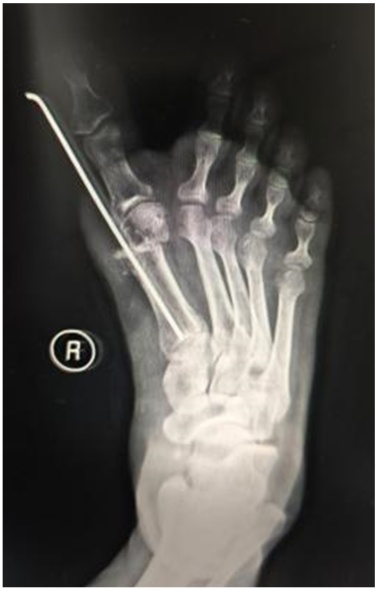

患者女,46岁。因“右足进行性行走疼痛、伴踇趾外翻畸形8月余”来我科就诊。专科检查:右侧第一跖趾关节外翻畸形(见图1(a)图1(b)),活动受限,拇囊部位压痛明显,无纵向叩击痛。第一跖趾关节松弛,活动后疼痛加重。前足功能AOFAS评分为45分,神经血管检查正常,其余肢体未见异常。既往史无特殊,检验结果未见异常。右足部X线片显示:右侧第一跖趾关节对位欠佳呈外翻改变,外翻角约33˚,第1、2跖骨间夹角约为9˚,第一近节趾骨近端可见骨质增生边尖(见图1(c))。入院诊断:右足拇外翻合并第一跖趾关节半脱位。完善相关检查后,行右足拇外翻切开截骨矫形克氏针内固定术。手术过程:麻醉生效后,患者取仰卧位,绑止血带,右下肢常规消毒铺巾,打止血带,C臂透视确认截骨位置,截骨位置靠近跖骨颈的内侧隆起处。皮肤切口:取右足背内侧第一跖趾关节处纵切口,切一长约2 cm皮肤切口。操作过程:电刀分离皮下组织至关节囊,电凝止血,切除增生关节囊,显露内侧跖趾关节,用摆据距跖骨远端2 cm处垂直于跖骨干横向截骨,将跖骨头向外侧推移,将第1根金属骨针沿远端截骨断端前内侧皮下置入并从拇趾趾甲近端内侧皮缘穿出,将布巾钳插入跖骨截骨近端髓腔,再从拇趾趾甲内侧将金属骨针置入跖骨干髓腔基底部内固定,透视确认足拇外翻畸形矫形满意,将第2根金属骨针从跖骨内侧缘距离跖骨近端截骨面1 cm处上斜形插入,从远端截骨面中点穿过,从跖骨远端外侧皮质穿出(见图1(d)图1(e)),固定截骨远端,C臂透视见拇外翻纠正,内固定位置可(见图1(g))。逐层缝合切口,以敷料固定包扎保护拇趾于中立位(见图1(f)),术后第2天复查X线(见图1(h))。术后6周来院拆除第2根金属骨针后,复查X线示恢复可(见图1(i)),术后7周来院拆除第1根金属骨针,复查X线片示恢复可(见图1(j)),术后3月我院复查足部情况(见图1(k))。

(a) (b) 术前右足外观;(c) 术前片X线片:右足中度拇外翻并第一跖趾关节半脱位;(d) 术中克氏针固定位置;(e) (f) 皮肤切口:右足背内侧第一跖趾关节处纵切口,切一长约2 cm;(g) C臂透视确认脱位复位满意,内固定位置可;(h) 术后右足正侧位x片显示:第一跖趾关节对位良好,跖骨断端对线可,轻度向内移动约1/4;(i) 术后6周患者右足部X线复查情况;(j) 术后7周右足部X线复查情况;(k) 术后3月右足部复查情况。

Figure 1. Patient’s imaging data

1. 患者影像学资料